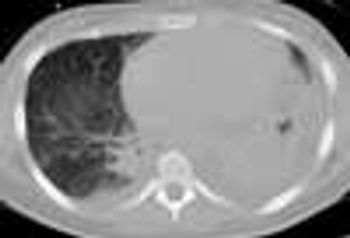

A 56-year-old was seen in the ED after 4 days of hemoptysis and intermittent left chest pain. He also complained of exertional dyspnea and arthralgias. He had been treated for “pneumonia” twice during the past month. Histories were unremarkable.